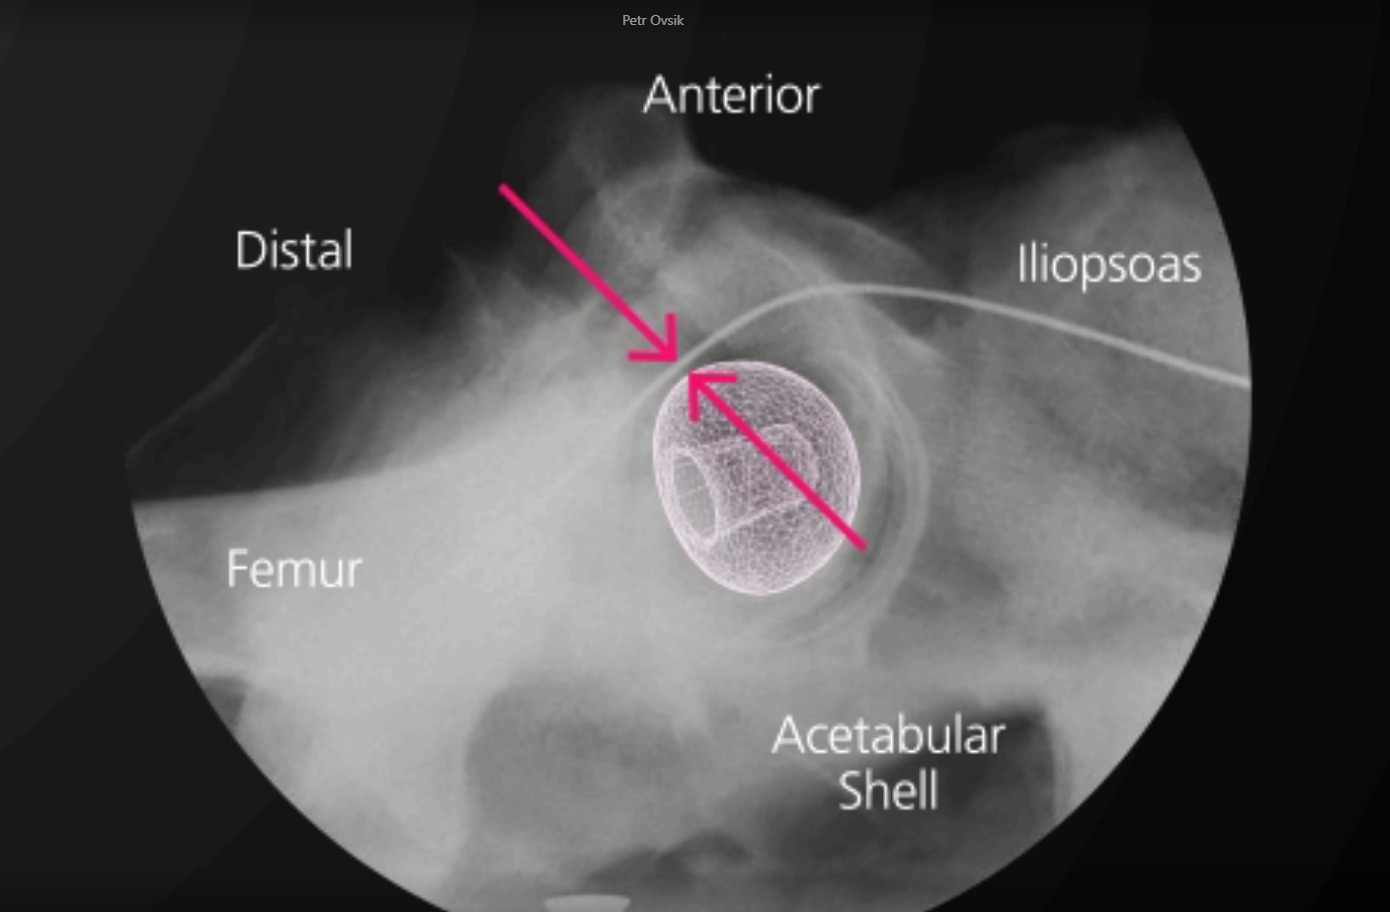

BIOLOX CONTOURA® ist ein konturierter keramischer Femurkopf, der die anatomische Form des proximalen Femurs nachahmt.

Beim BIOLOX CONTOURA® bleibt das Profil eines herkömmlichen Implantats im halbkugelförmigen Teil oberhalb des Äquators erhalten. Der distale Teil des Femurkopfes, unterhalb des Äquators, ist jedoch mit einem kleineren Radius konturiert. Dies verfolgt das Ziel, das Volumen des Materials, das mit dem Weichteilgewebe in Kontakt kommt, zu reduzieren. Die Gegenüberstellung eines 36mm BIOLOX CONTOURA® Hüftkopfes und eines 32mm konventionellen Keramikkopfes zeigt die Volumenreduktion von BIOLOX CONTOURA®.